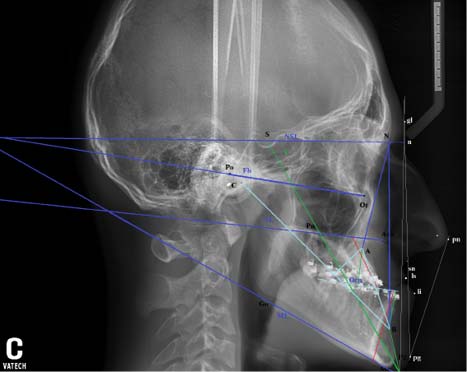

Рис. 1. Профильная телерентгенограмма головы пациента К.В. 16 лет в начале дохирургического ортодонтического лечения

При анализе профильной ТРГ, полученной до начала лечения (рис. 1), показатели профилометрии (табл. 1) оказались характерными для клинических признаков патологической окклюзии пациента К. Значение ∠T=–8° (в норме ∠T=10°) соответствовало вогнутому скелетному профилю лица и ретропозиции подносовой (sn) точки относительно плоскости Pn и точки Pg. Изучение эстетичности лица пациента К. на профильной ТРГ головы по методу Rickets также выявило нарушение. Эстетическая линия E-plane, проведённая через кончик носа pinnasale (Pn) и наиболее выступающую точку Pg, от положения выступающих точек губ оказалась намного дальше (7,5 мм) в сравнении с нормой (0–2 мм) по Rickets.

Результаты краниометрии (см. табл. 1) позволили уточнить нарушения положения челюстей относительно переднего отдела основания черепа. Значения углов (∠SNA=78,9°; ∠SNB=92,5°; ∠ANB=13,6°) указали на ретропозицию передней точки апикального базиса верхней (А) и пропозицию передней точки апикального базиса нижней (В) челюстей относительно основания черепа (SN). Угол (∠I) наклона плоскости основания верхней челюсти к плоскости Pn, перпендикулярной плоскости переднего отдела основания черепа (SN), был в пределах нормы. Угол горизонтали (∠H), отражающий наклон траго-орбитальной линии, или франкфуртской горизонтали (FH), к Pn, перпендикулярной плоскости переднего отдела основания черепа (SN), оказался меньше нормы по Schwarz на 1,0°.

Показатели гнатометрии (табл. 2) выявили отклонения взаимоположения челюстей от нормы. Проекция (А') передней точки апикального базиса верхней челюсти (А) на окклюзионную плоскость (Ocp) оказалась дистальнее проекции (В') передней точки апикального базиса нижней челюсти (В) на окклюзионную плоскость (Ocp) на 19,5 мм (Wits-число), что подтвердило факт достоверного отличия взаимоположения челюстей от нормы (Wits-число в норме от 0 до 2,0 мм).

Для определения пропорциональности отделов лицевого скелета изучили соответствие сагиттальных размеров верхней (NL) и нижней (ML) челюстей переднему отделу (SN) основания черепа. Полученный результат (мм) (SN:NL:ML=63:43:76=1,0:0,68:1,21) отличался от нормы по Schwarz (SN:NL:ML=1,0:0,7:1,05) и выявил несоответствие сагиттальных размеров челюстей друг другу и переднему отдела основания черепа, верхнюю микрогнатию и нижнюю макрогнатию.

Учитывая, что положение передней точки подбородка (Pg) зависит от его размеров, по методу Sassouni было определено расстояние от Pg до перпендикуляра из точки В к нижнечелюстной плоскости. Величина подбородочного выступа оказалась 7,0 мм — в пределах нормы (6–9 мм).

На ТРГ пациента К. значения ∠SNA, ∠SNB и ∠ANB показали сочетание пропозиции нижней челюсти с ретропозицией верхней челюсти относительно друг друга и переднего отдела основания черепа. Увеличение размеров нижней челюсти, нарушение пропорциональности сагиттальных размеров челюстей и переднего отдела основания черепа (NSL:NL:ML=1,0:0,68:1,21) в сравнении с нормой (1,0:0,7:1,05) по Schwarz усиливали выраженность скелетных нарушений (см. табл. 1). Сочетание признаков нарушения положения и размеров челюстей относительно друг друга и переднего отдела основания черепа, на наш взгляд, — значимые для планирования лечения диагностические параметры.

Изучали наклон передних зубов (L1 и U1) относительно плоскостей основания верхней (NL) и нижней (ML) челюстей. Угол наклона верхних резцов относительно основания верхней челюсти (∠U1-NL=56,0°) отличался от нормы на 9° (норма 70±5°). Наклон нижних резцов (∠L1-ML= 84,1°) оказался в пределах нормы по A.M. Schwarz.